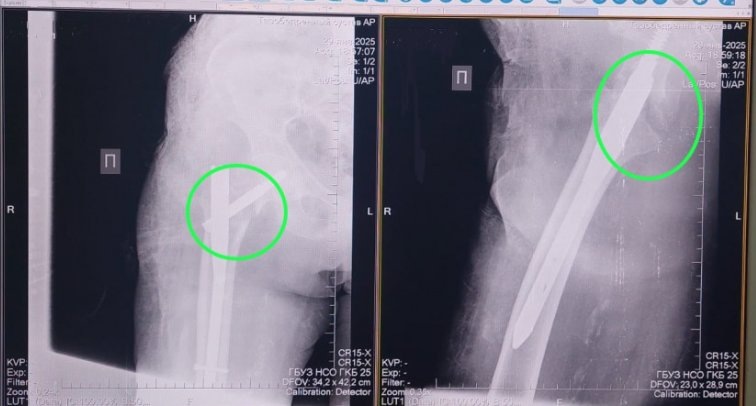

В ГКБ №25 пациентке провели остеосинтез — сопоставили костные отломки и зафиксировали их металлической конструкцией. Сейчас женщина уже дома, перед выпиской ей приобрели ходунки, и она получает дозированную нагрузку на сустав. По словам врачей, быстрая активизация пациента после операции значительно улучшает прогноз восстановления.